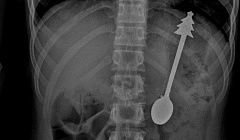

14-сантиметровую ложку проглотил ребенок в Оренбургской области

Ему провели срочную операцию.

Происшествия

8 фев, 10:00